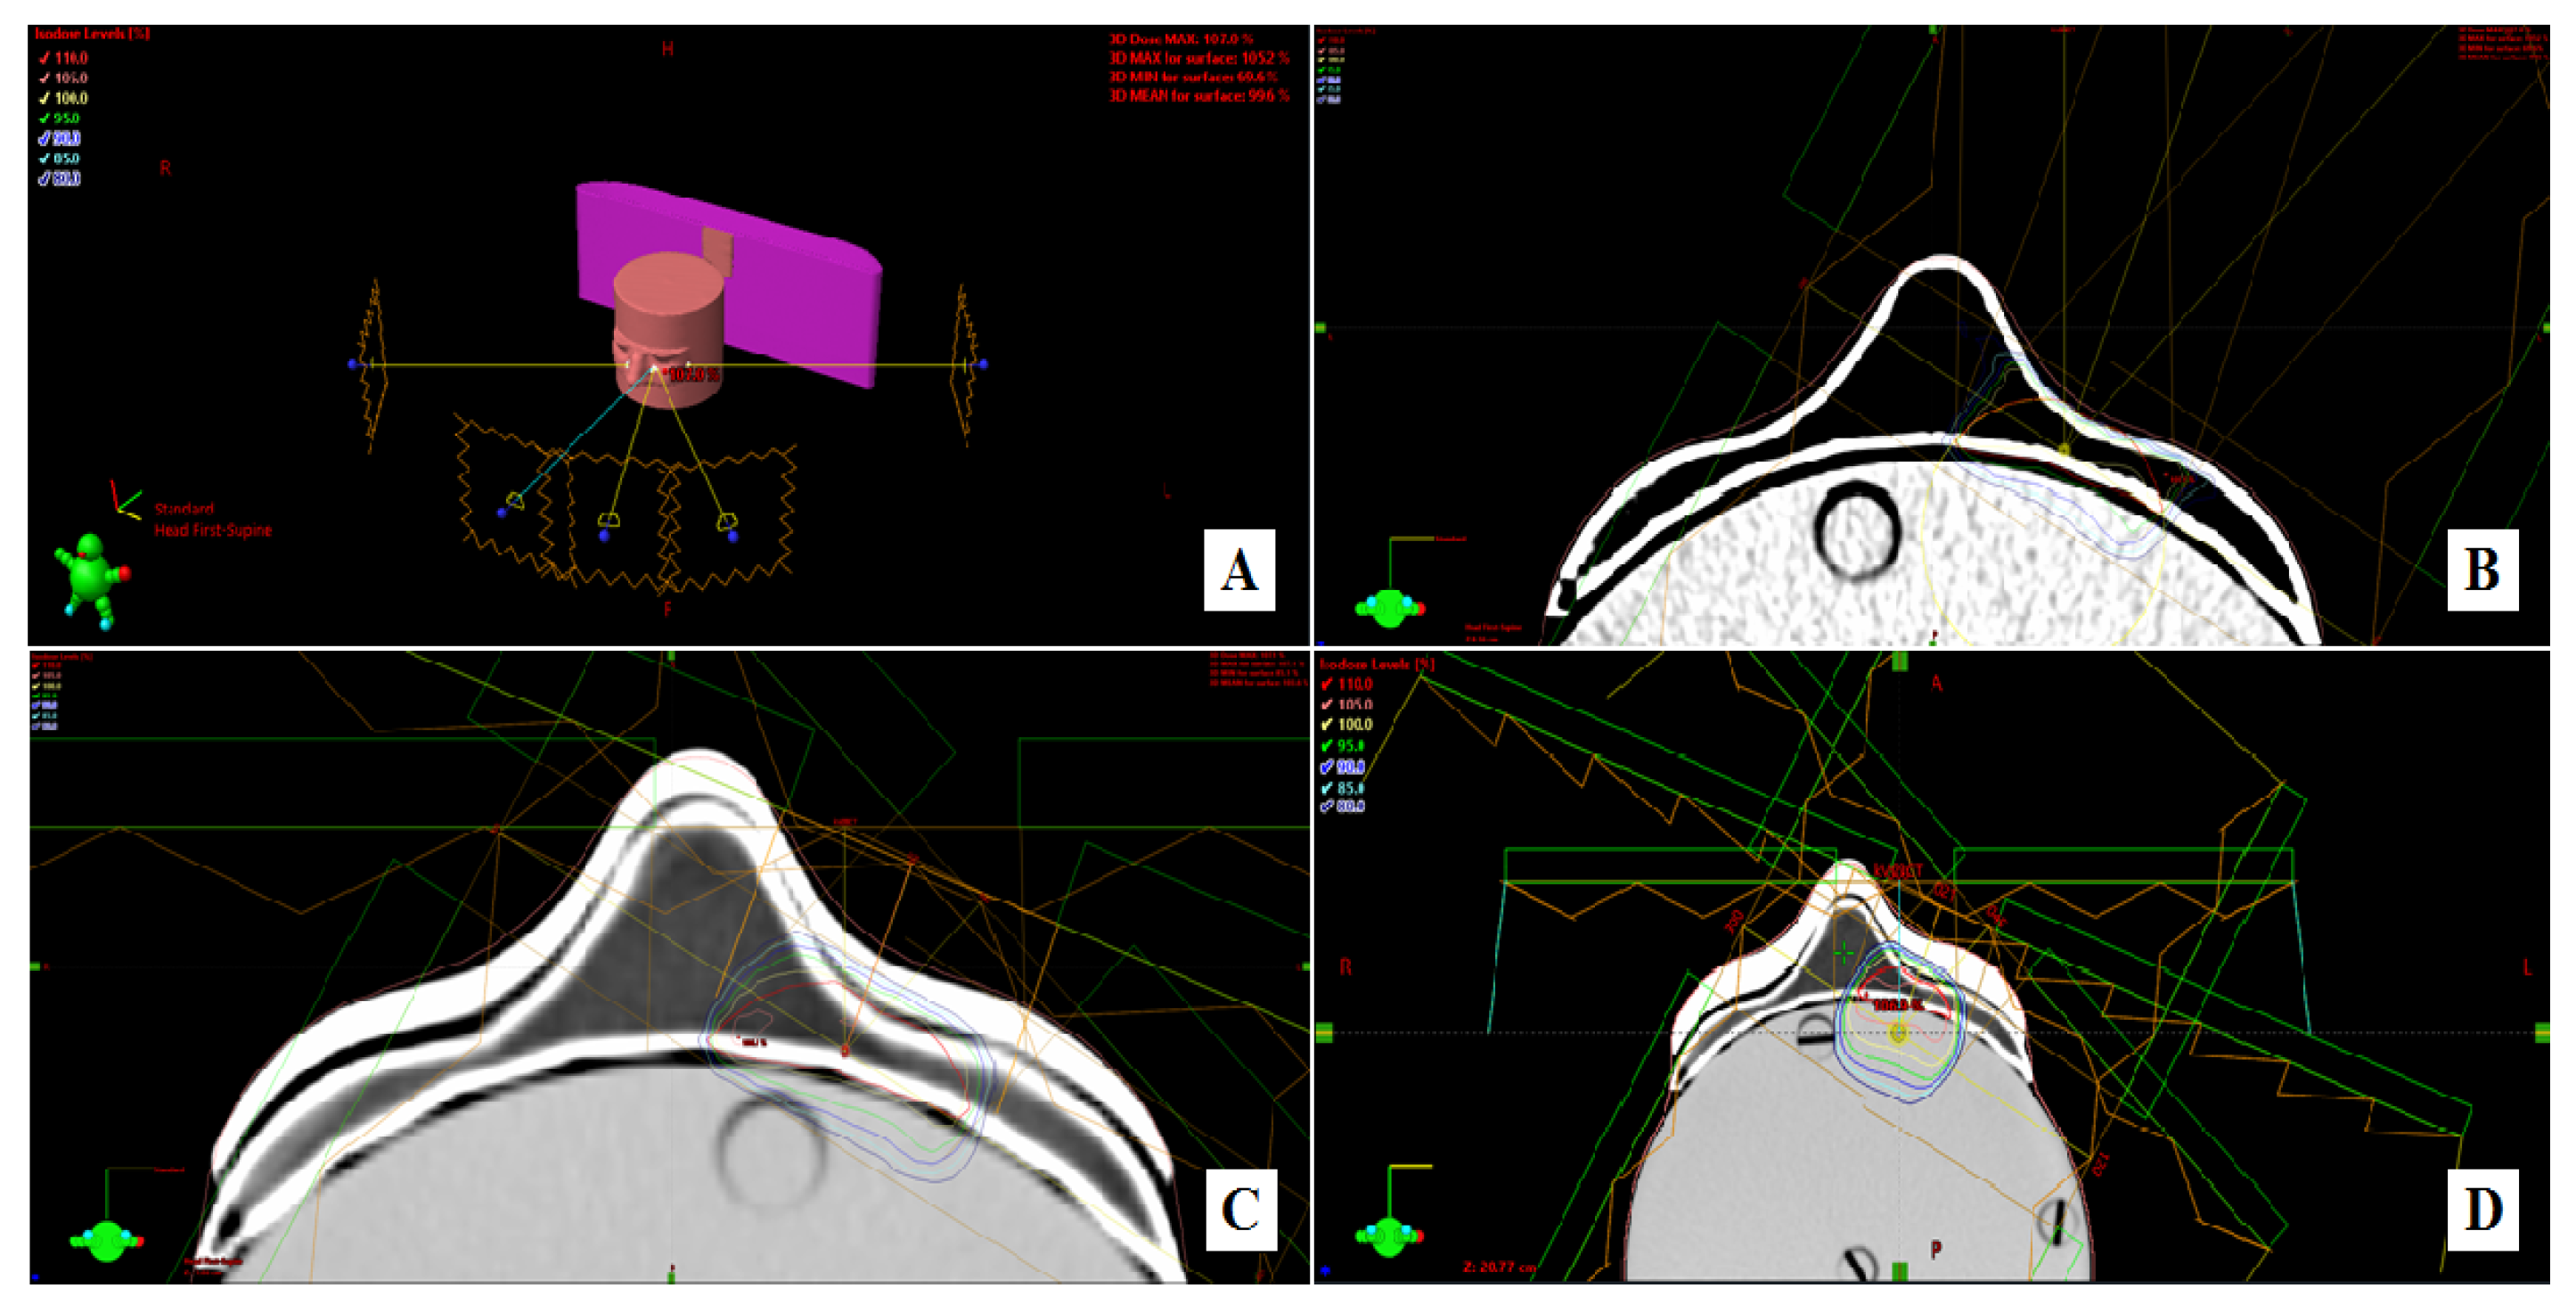

2.1. Development of Personalized 3D Devices

2.4. Dosimetric Evaluation

3.3. In Vitro Dose Verification Using 3D-Printed Devices